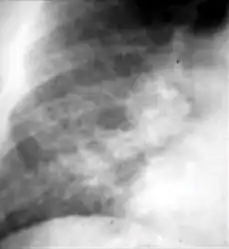

Chest x-ray showing coarse reticulonodular densities on the lower right lung of post-primary pulmonary TB. -